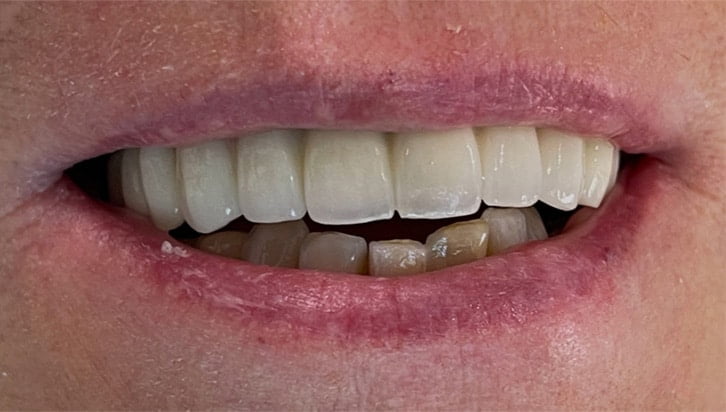

Dental Implant Cases

Aberdeen Implant Centre

Beautiful new smiles created at the Dental implant centre